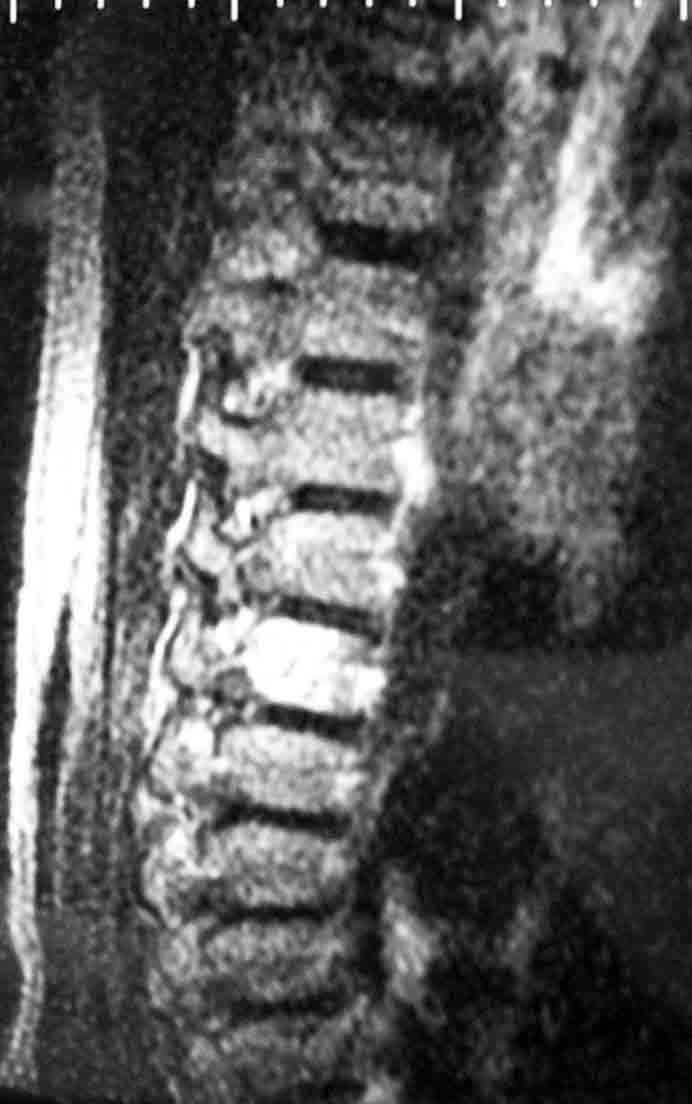

У пациентки 50 лет, сотрудницы нашего центра проводили обследование по поводу хронических болей в поясничном и грудном отделе позвоночника.

Помимо распространённого остеохондроза и деформирующего спондилёза обнаружили гемангиому 1/2 тела Th-9 позвонка.

Какова может быть тактика лечения гемангиомы? Локальной болезненности при пальпации 9-го грудного позвонка нет, боли носят распространённый характер, не привязаны к Th-9.